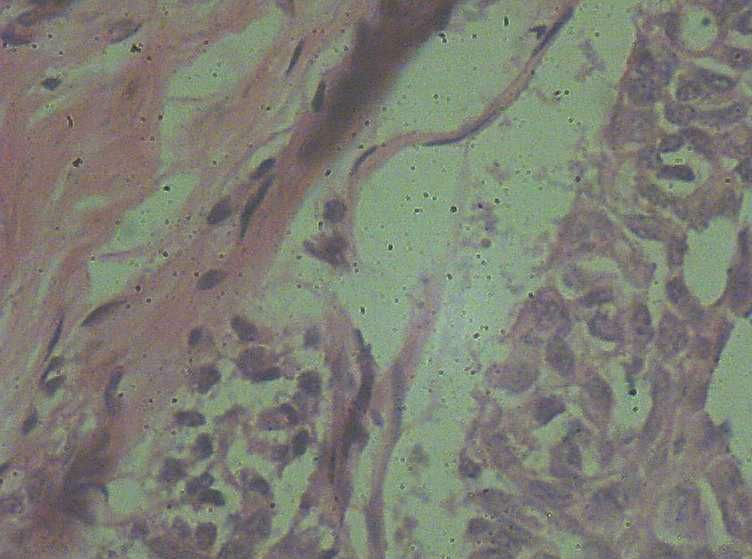

快捷回复

女41岁,左腺包块。肉眼:不整形囊壁样组织,大小2*1.6*0.3CM,壁厚0.1—0.3,未触及结节,未见出血及坏死。